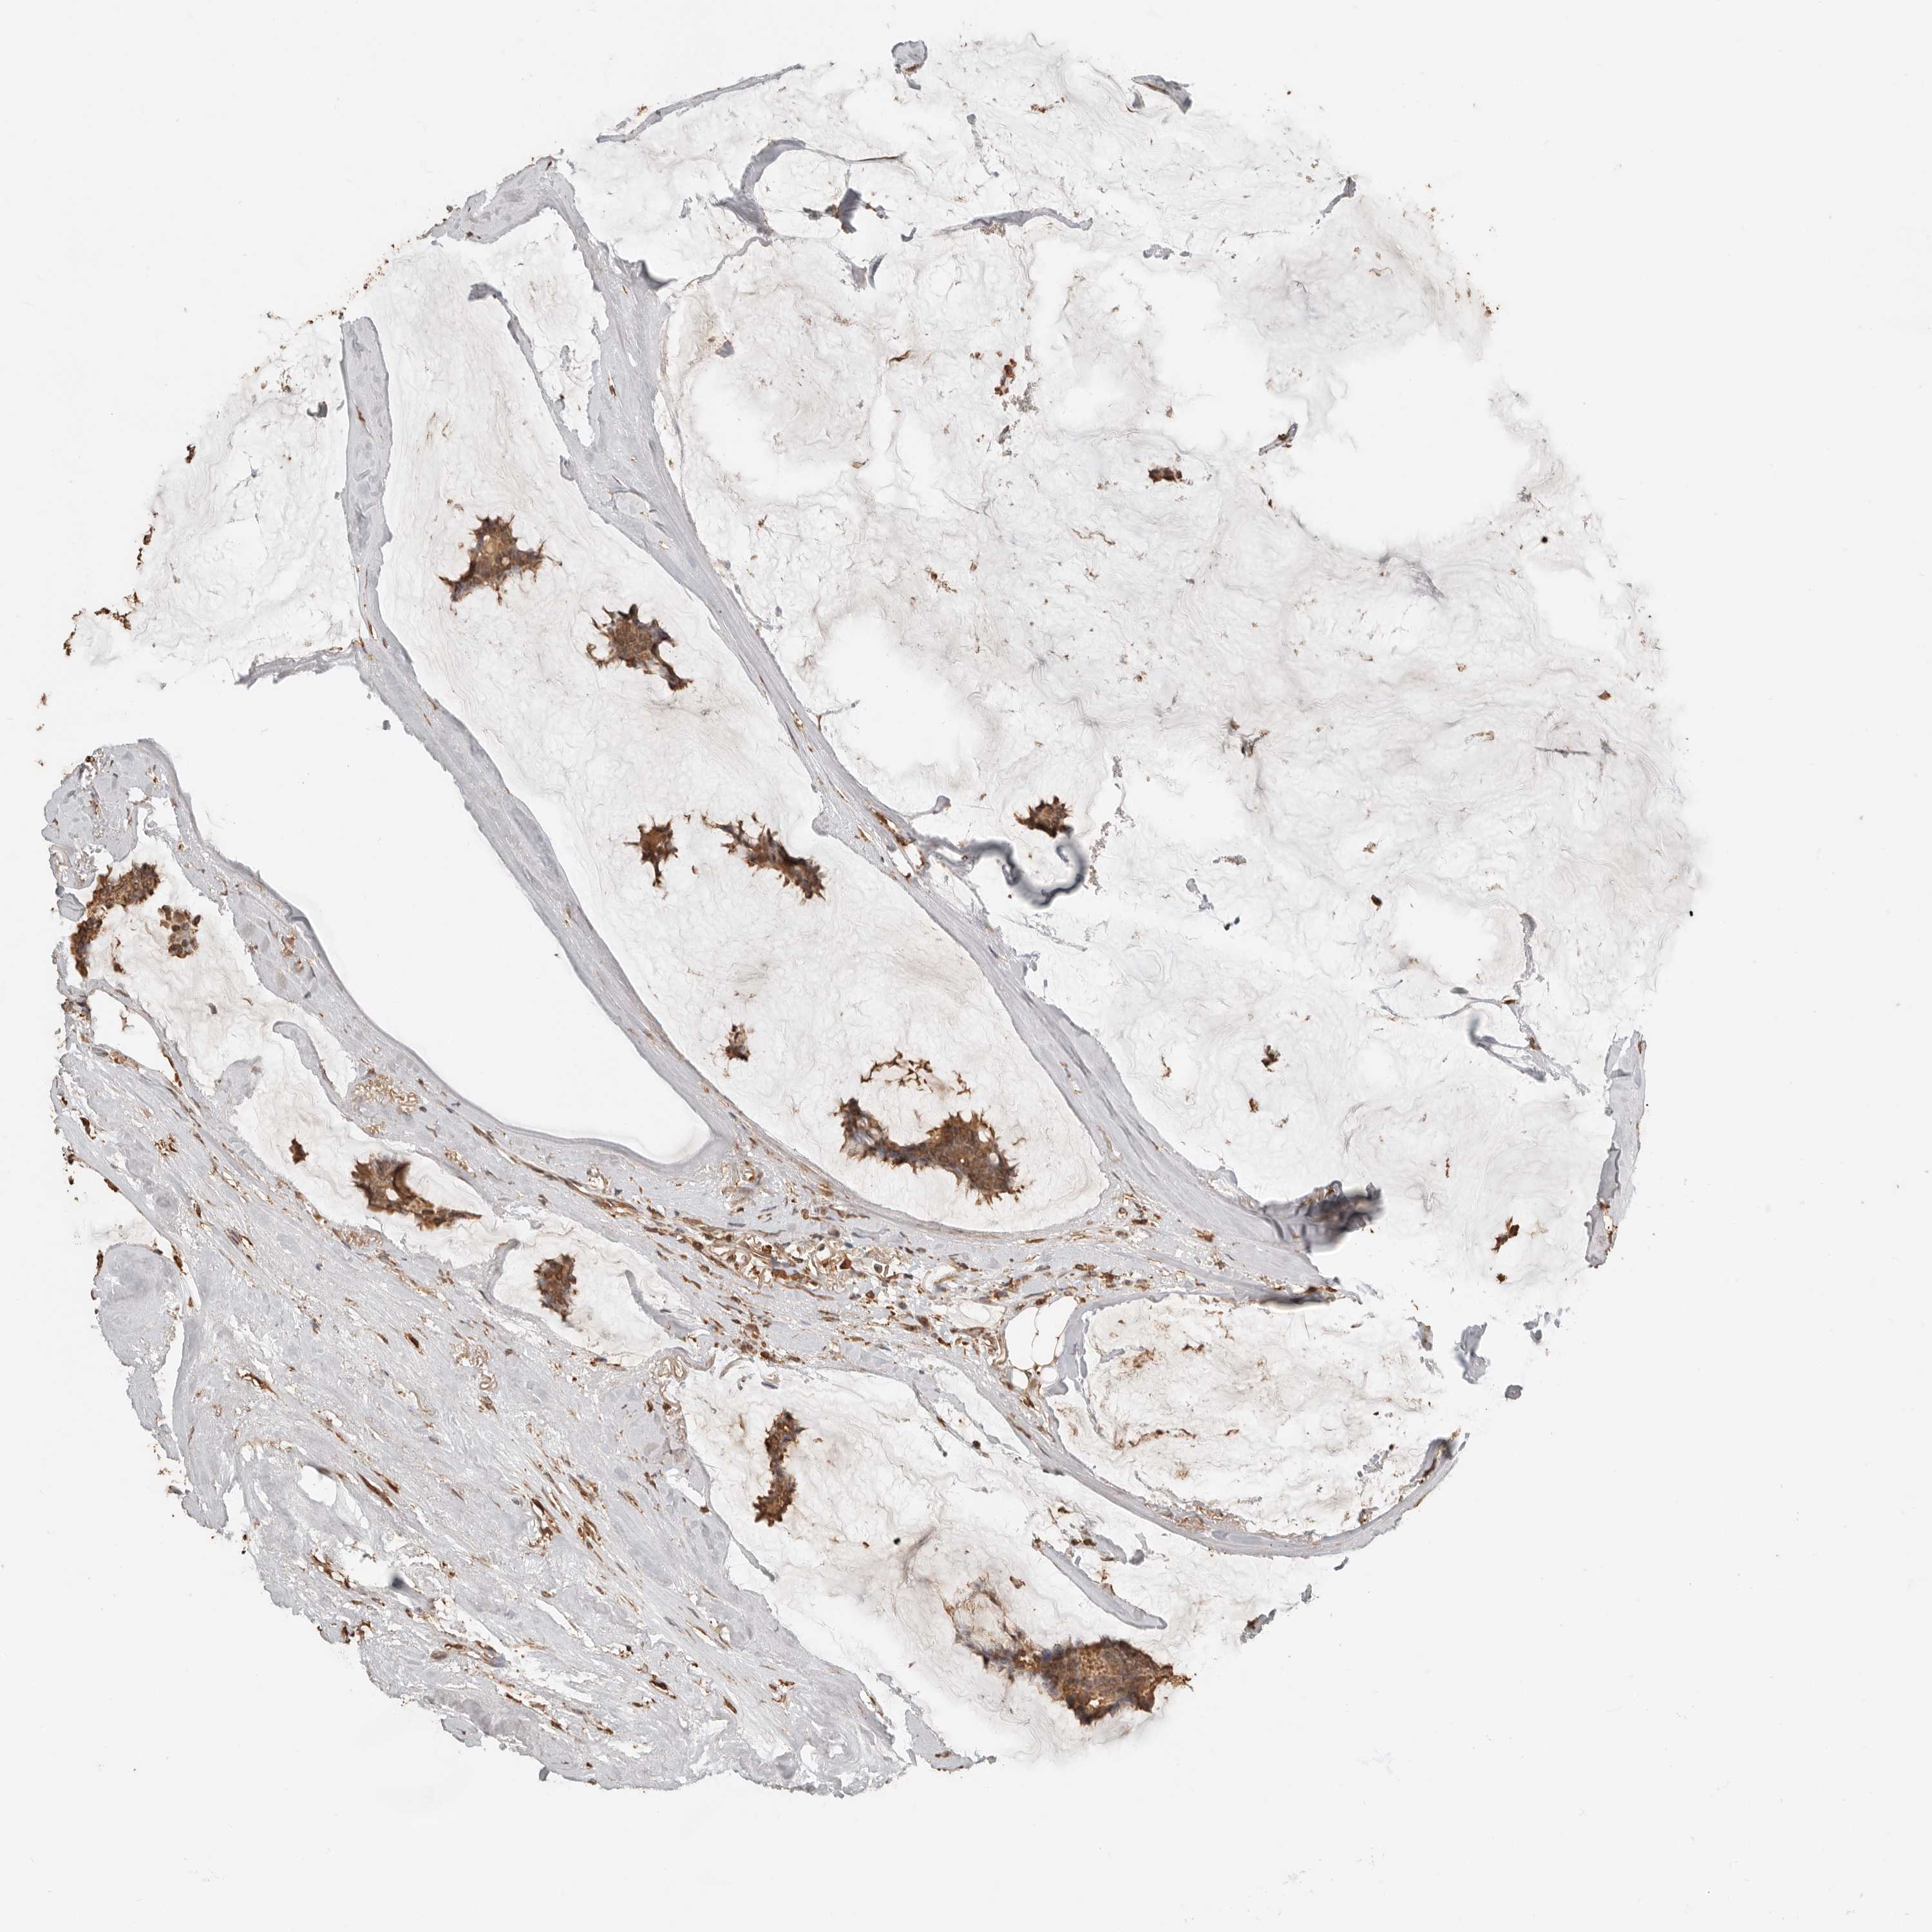

BRCA TCGA BRCA VALIDATION PROTEIN EXPRESSION